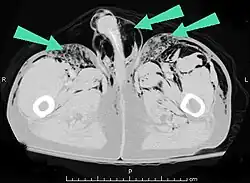

Les cas importants d'emphysème sous-cutané sont faciles à diagnostiquer en raison des signes caractéristiques de l'affection. Dans certains cas, les signes sont subtils, ce qui rend le diagnostic plus difficile. L'imagerie médicale est utilisée pour diagnostiquer la maladie ou confirmer un diagnostic établi à l'aide de signes cliniques. Sur une radiographie du thorax, l'emphysème sous-cutané peut être vu comme des stries radiotransparentes dans le modèle attendu du groupe de muscles principaux du pectoral. L'air présent dans les tissus sous-cutanés peut interférer avec la radiographie du thorax, ce qui peut masquer des affections graves comme le pneumothorax. Elle peut également réduire l'efficacité de l'échographie thoracique. D'autre part, comme l'emphysème sous-cutané peut être visible sur les radiographies du thorax avant un pneumothorax, sa présence peut être utilisée pour déduire celle de cette dernière lésion. L'emphysème sous-cutané peut également être observé sur les scanners, les poches d'air apparaissant comme des zones sombres. Le scanner est si sensible qu'il permet généralement de trouver l'endroit exact d'où l'air pénètre dans les tissus mous. En 1994, M. T. Macklin et C. C. Macklin ont publié d'autres aperçus sur la physiopathologie du syndrome de Macklin spontané survenant à la suite d'une grave crise d'asthme. La présence d'un emphysème sous-cutané chez une personne qui semble très malade et fébrile après une crise de vomissements suivie d'une douleur thoracique gauche est très évocatrice du diagnostic du syndrome de Boerhaave, qui est une urgence vitale causée par une rupture de l'œsophage distal. L'emphysème sous-cutané peut être une complication de l'insufflation de CO2 avec la chirurgie laparoscopique. Une augmentation soudaine du CO2 en fin de marée après la hausse initiale qui se produit avec l'insufflation (les 15-30 premières minutes) devrait faire suspecter un emphysème sous-cutané. Il est à noter que l'oxymétrie de pouls et la pression des voies aériennes ne varient pas dans l'emphysème sous-cutané, contrairement à l'intubation endobronchique, au capnothorax, au pneumothorax ou à l'embolie au CO2.

Dans une pneumonectomie, dans laquelle un poumon entier est retiré, le moignon bronchique restant peut laisser fuir de l'air, une condition rare mais très grave qui conduit à un emphysème sous-cutané progressif. [8] L'air peut s'échapper de l'espace pleural par une incision pratiquée pour une thoracotomie afin de provoquer un emphysème sous-cutané. [8] À de rares occasions, le cas peut résulter d'une chirurgie dentaire, généralement due à l'utilisation d'outils à grande vitesse entraînés par de l'air. [24] Ces cas se traduisent généralement par un gonflement indolore du visage et du cou, avec un début immédiat, le crépitement typique de l'emphysème sous-cutané, et souvent avec de l'air sous-cutané visible aux rayons X. [24]